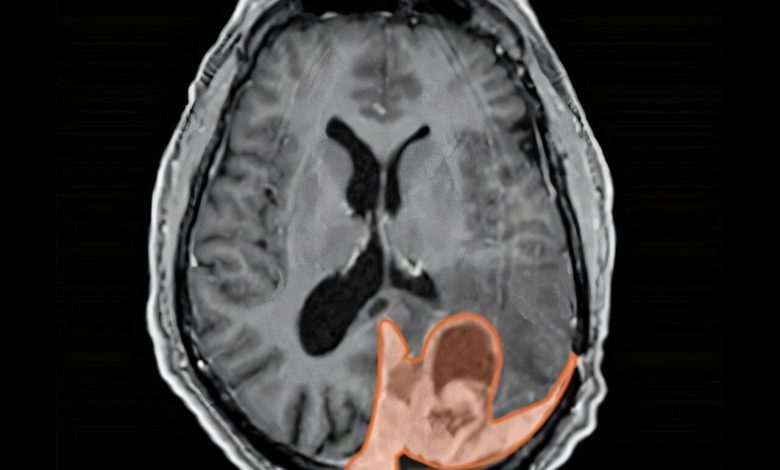

Tomografia cerebral mostrando um meningioma destacado em laranja. Crédito: Centro de Tumor Cerebral da UCSF

Uma em cada quatro mulheres sexualmente activas utilizou métodos contraceptivos injectáveis, administrados no músculo por um médico, mas muitas podem não ter conhecimento da sua associação com o meningioma, o tumor cerebral mais comum em adultos. Na Europa e no Canadá, o medicamento é obrigado a trazer um aviso – mas não nos EUA